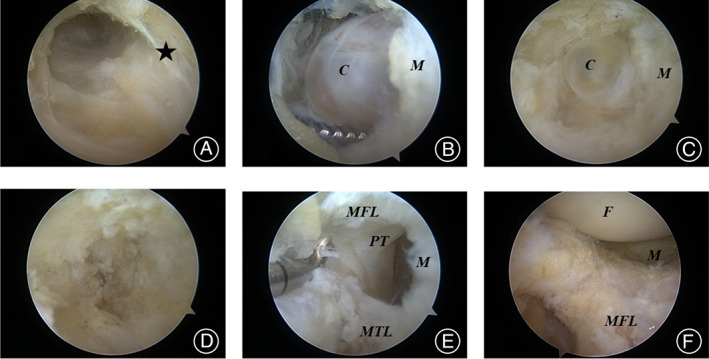

Compared with the traditional arthroscopic cyst excision, the modified arthroscopic cyst excision can preserve the stable structures of the meniscus synovial rim and can clearly show the inner and surrounding tissues of the parameniscal cyst. The modified procedure is shown in Figure 2. Arthroscopic photographs show the whole process in Figure 3.

FIG. 3.

Images under arthroscopy during surgery. (A) Passageway to the cyst was made by shaver through the anterolateral fat pad at the level of the meniscus. (B) Blunt dissection exposes the cyst. (C) Exposure of small deep cysts after excision of large cysts. (D) Exposure of the popliteal tendon after complete excision of the cyst. (E, F) Situation after cyst removed. Asterisk: level of meniscus; MFL: meniscofemoral ligament; M: meniscus; MTL: meniscotibial ligament; C: cyst; F: femur; PT: popliteal tendon.